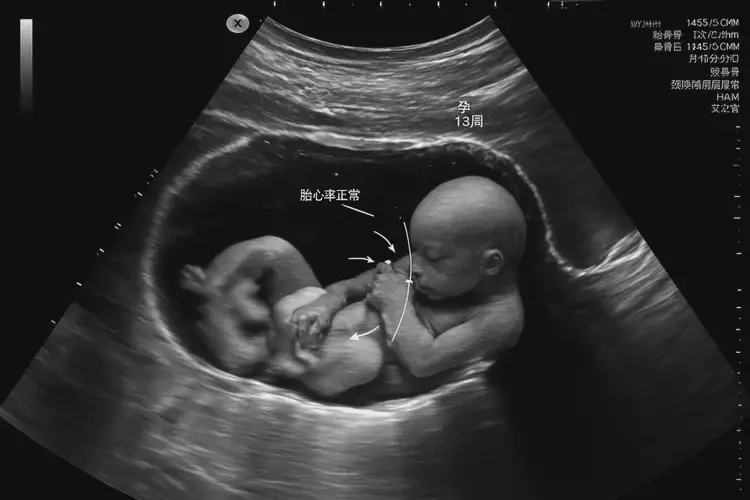

孕13周2天胎心100多有危險(xiǎn)嗎

胎心率在孕13周2天時(shí)為100多次/分鐘,通常屬于正常范圍。

在孕13周2天時(shí),胎兒的胎心率通常在110-160次/分鐘之間波動(dòng)。胎心率為100多次/分鐘,雖然略低于平均水平,但并不意味著一定有危險(xiǎn)。如果胎心率持續(xù)低于110次/分鐘,或者出現(xiàn)其他異常情況,建議及時(shí)咨詢醫(yī)生以獲取專業(yè)建議。

孕13周2天胎心100多有危險(xiǎn)嗎(圖1)